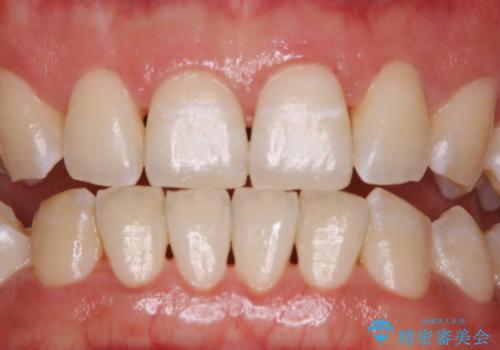

ホワイトニングせずにPMTCで明るい口元に

- ホワイトニングを考えているとのことで久しぶりに来院された方です。歯石やプラークの付着があったため、まずはPMTC60分コースを行いました。

施術後には、現状で満足とのことだったため今後は定期的なクリーニングを行っていくこととなりました。

ホワイトニングを考えている場合でも、状態によってはクリーニングを行うことでご希望の状態になることもあります。

PMTCでは、プラークや歯石、着色などを徹底的に除去します。

まずは、ご自身本来の歯の状態にしてからホワイトニングを行うか検討してもらうことをおすすめします。